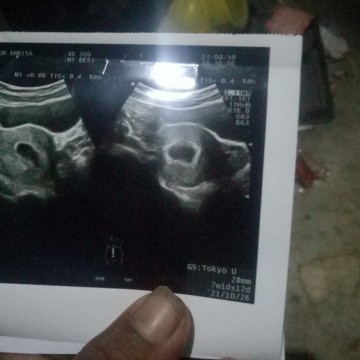

Kandungan belom berkembang kenap bun #

baru 7w bun.. coba usg 2 minggu lagi..

sya 7w udh ad janinx bund kcil

nah.. klo sya kmren usg di bidan udah keliatan bun janinx kcil 7w